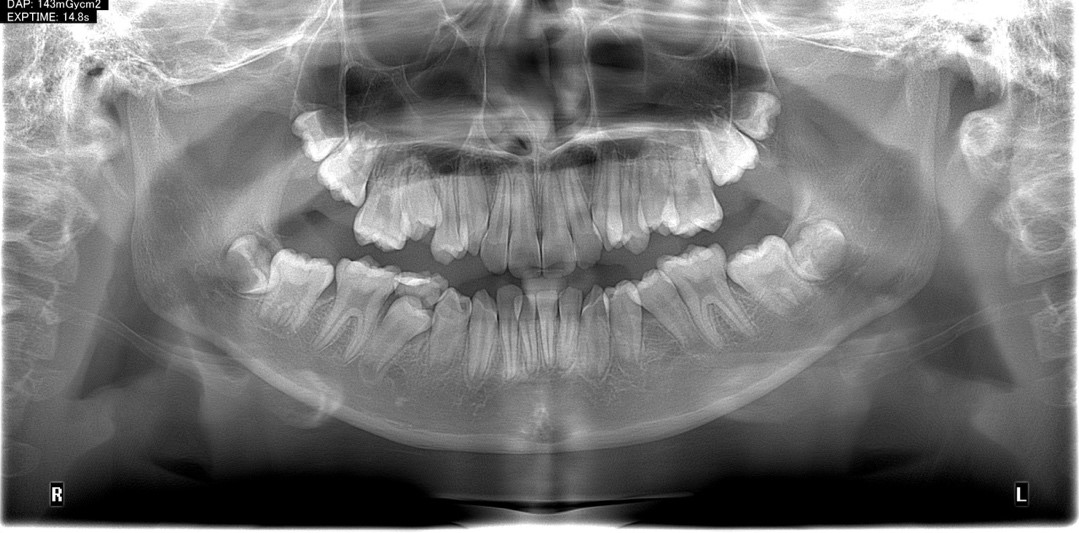

Bước này là bước đầu tiên của quy trình niềng răng, các nha sĩ sẽ tiến hành thăm khám, tư vấn và chụp phim, sau đó đưa ra các chỉ định như nhổ răng hay điều trị sâu răng trước khi tiến hành niềng răng. Trang thiết bị hỗ trợ cho bước này sẽ gồm có:

· Máy chụp phim toàn cảnh và sọ nghiêng.

· Phần mềm vi tính để thu thập dữ liệu và phân tích tình trạng lệch lạc các răng và hàm.

Đây là một trong những bước quan trọng nhất, bước này sẽ giúp cho người nha sĩ có thể vạch ra được lộ trình niềng răng cho bệnh nhân một cách chính xác nhất.